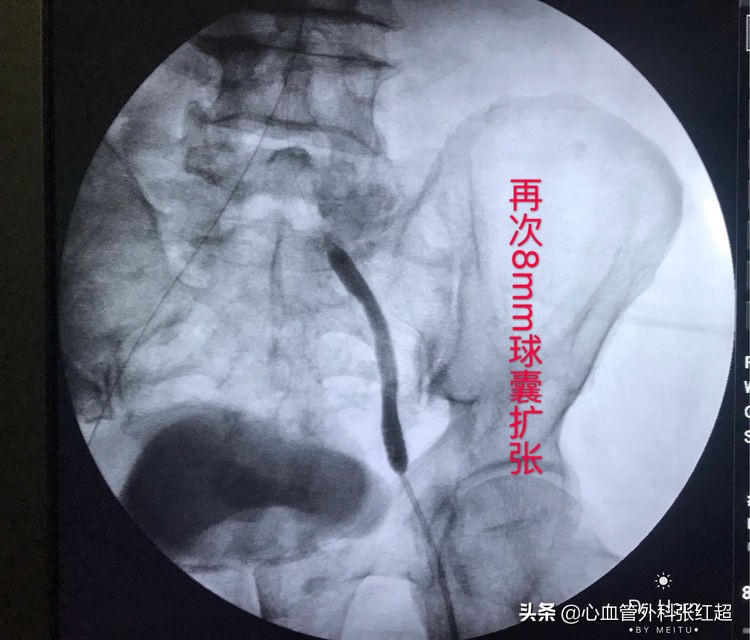

屈曲部稍有残余狭窄。不用硬扩,支架可以在术后贯性序扩。

放两枚支架更容易保证远端释放到位